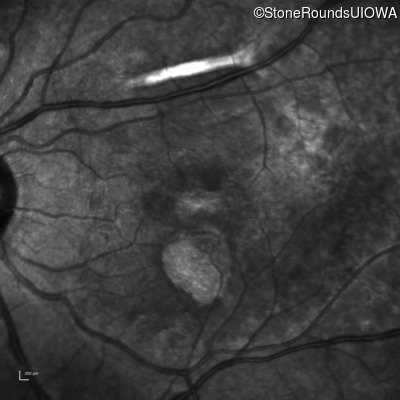

Infrared Fundus Photograph - Right - 20/40 -1

Exemplar

Infrared Fundus Photograph - Left - 20/20 -2